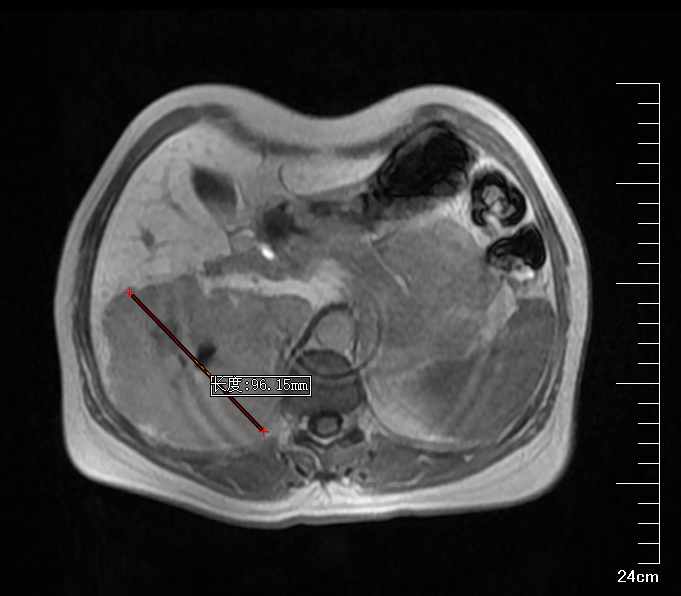

肝右叶巨大血管瘤CT

肝胆胰外科古松钢副主任在查看患者及外院CT报告后,认为患者右肝巨大肿物,大小约9*10*9.5cm,考虑为肝右后叶巨大血管瘤,需积极行手术治疗,否则血管瘤有破裂出血可能。将钱女士收治入院后,进一步完善腹部增强CT,评估患者肝储备功能以及心肺功能。